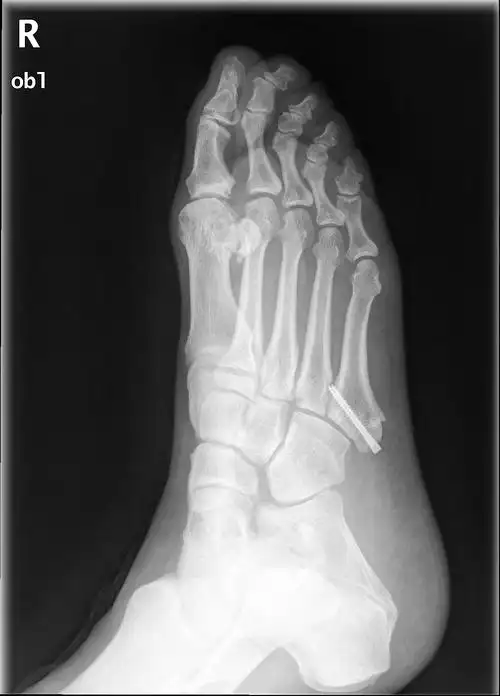

右脚第五跖骨基底部骨折

足部骨折患者的x线照片

6岁 女 左足第五跖骨远端骨折

第5跖骨基底部骨折